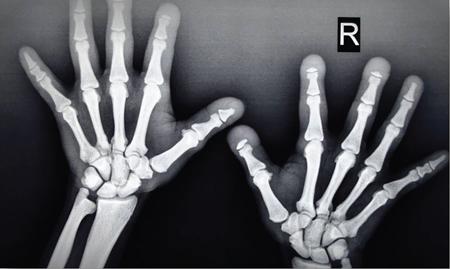

MISCELLANEOUS PAEDIATRIC RADIOGRAPHY – TECHNIQUES AND INTERPRETATION: SKELETAL SURVEY Padma V. Badhe The skeletal survey, generally performed in children, is a set of radiographs done in order to evaluate the entire skeleton. A skeletal survey, commonly used to evaluate skeletal dysplasias, acquired metabolic disorders and suspected child abuse, is still the key radiological investigation for the same. Hence, an explicit understanding of the technique along with the common disorders forms the basis of making a diagnosis in these paediatric pathologies. A skeletal survey is done for various skeletal dysplasias, non-accidental injury (battered baby syndrome) and suspected child abuse. It can also be done in cases of metabolic bone diseases, disseminated infections, multiple myeloma, eosinophilic granuloma. It is also used in evaluation of metastatic bone diseases and polyarticular arthropathy. Orthogonal views of the skull, spine, pelvis and one extremity are taken, preferable in standing position. For preterm babies/newborns, AP and lateral views of babygram may be taken. Projections: For skeletal dysplasias: Additional views: Both extremities may be taken if epiphyseal abnormalities and limb asymmetry is present. Focused views for specific pathologies may be taken. When a diagnosis remains uncertain, 1 year follow up is usually recommended. For preterm babies/newborns: AP and lateral views of babygram may be taken with additional specific views for extremities. For suspected non-accidental injury (NAI): AP and oblique view of chest is taken for better evaluation of the ribs. AP view of abdomen with pelvis. Both upper and lower limbs are evaluated. In lower limbs, two projections in AP and lateral (one with both femur including hip and knee joints; and another for foot and ankle) is taken. AP and lateral views of whole spine, skull. Oblique view of hands. A babygram should be avoided in cases of NAI, as subtle fractures are easily missed. Proper legal documentation while taking the views is very important and ideally two health care professionals must be present. For metabolic disorders: entire skeletal survey is usually not required. Specific views of hands, knees and spine may be taken with additional views depending on the suspected pathology. Centring point: Varies according to the part being examined. Angulation, collimation and orientation: Varies according to the part being examined. Images must be well collimated to obtain lower radiation dose. Detector size: Varies according to the part being examined: 8″ × 10″, 10″ × 12″, 11″ × 14″. Exposure: Ideally high kVp images are taken to reduce radiation dose. But in suspected NAI, low kVp/high mA images are recommended to better demonstrate findings. SID (Source Image Distance):100 cm Grid: Grids are not routinely used to image spine, pelvis, skull and abdomen in children. Radiation dosage: 0.3–3 mSv Essential image characteristics: Adequate spatial resolution, high signal to noise ratio, low kVp (50–70) for high contrast should be done. Excellent bone and soft tissue details are required. The presentation of skeletal dysplasia can range anywhere from minimal stunting of growth and bowing of limbs to severe dwarfism and multiple fractures. Knowledge of the commonly encountered dysplasias with an approach to arrive at a diagnosis is vital in any Radiologist’s practice The following flow chart summarizes the classification of important skeletal dysplasia: The following table summarizes the various dysplasias affecting the axial skeleton: TABLE 7.5.1.1 The following flow chart summarizes the working approach to skeletal dysplasias: Osteopetrosis (Albers-Schonberg disease/Marble bone disease) (Fig 7.5.1.1): Osteopetrosis clinically presents with anaemia/thrombocytopenia or cranial nerve compression. Radiological features include generalized increase in bone density with loss of medullary space. However, cortico-medullary appreciation with cortical thinning is also rarely seen. Bone within bone appearance with Erlenmeyer flask deformity is also noted. Pyknodysostosis (Figs. 7.5.1.2 and 7.5.1.3): patient presents with short stature. Unlike osteopetrosis, there is no anaemia. Radiographs show generalized increase in bone density with preserved medullary canal. There is mandibular hypoplasia with obtuse angle. Acro-osteolysis is also a feature. Dental caries with osteomyelitis of the jaw may be seen. Sclerosing dysplasia presenting as wavy undulating new bone formation. Usually monomelic, lower limb and along one side. The classic appearance is described as Dripping candle Wax sign. It is a Sclerosing dysplasia with radiological features of symmetric juxta-articular involvement in epimetaphyseal region. They are 1–10 mm in diameter and uniform in size. No metabolic activity is seen on bone scans. This skeletal dysplasia shows diffuse decrease in bone density with paper-thin cortex. Fractures heal in normal time but shows callus with poorly cellular matrix. Wormian bones and enlarged sinuses may be seen. Codfish vertebra (Biconcave vertebra) may be seen. Metaphyseal corner fractures are not seen in osteogenesis imperfecta that helps to differentiate it from battered baby syndrome. There are four types of OI out of which type one is most common (Figs. 7.5.1.6 and 7.5.1.7). The radiological features of MPS include Osteopenia and Universal platyspondyly. The intervertebral disc spaces are maintained. Proximal pointed metacarpals is an important radiological finding. Hurler’s syndrome show anteroinferior beaking with short and wide metacarpals. Varus deformity of humerus is characteristically seen in Hurler’s syndrome (Fig. 7.5.1.8). Mental retardation & corneal clouding is seen in Hurler’s syndrome whereas these Hunter’s disease has normal intelligence with no corneal clouding. Morquio’s syndrome shows central beaking (Fig 7.5.1.9). This skeletal dysplasia shows normal bone density with rhizomelic limb shortening and normal trunk. Narrowing of spinal canal is classically seen with decrease in the Interpedicular distance caudally. Other radiological features include trident hand (separation of middle & third fingers), Champagne glass pelvis (short, flat ilia and small sciatic notch), bullet nose vertebra and overexpansion of skull with narrow foramen magnum (Fig. 7.5.1.10). This skeletal dysplasia is characterized by normal bone density with dwarfism and normal craniofacial skeleton. The interpedicular distance is normal. There is severe platyspondyly with anterior tonguing (disappears at older age). Other radiological features include increased disc space, short stubby metacarpals, small irregular epiphysis and widened metaphysis. Anterior tonguing is a feature of Pseudoachondroplasia. This form of skeletal dysplasia involves the spine and epiphyses (Fig. 7.5.1.11). There is normal bone density with rhizomelia. Spine and Pelvis can be involved. Premature osteoarthritis can be seen. The other characteristic features include Platyspondyly and small irregular epiphysis. There are two forms Spondyloepiphyseal dysplasia Congenital and Spondyloepiphyseal dysplasia Tarda. Spondyloepiphyseal dysplasia Congenita is Autosomal dominant and shows pear-shaped vertebrae. Spondyloepiphyseal dysplasia Tarda is X Linked recessive with heaped up vertebrae. It has two forms. The first form is Conradi Hunermann syndrome which is autosomal dominant characterized by asymmetric limb shortening with metaphyseal flaring (Fig. 7.5.1.12). The Autosomal recessive form is Fatal in first few years. Rickets: Rickets refers to deficient mineralization of the growth plate in the paediatric population due to deficiency of vitamin D. In an immature skeleton, there is abnormal mineralization at the zone of provisional calcification in the metaphysis due to osteoid deposition resulting in widening of the growth plate. The features of rickets include fraying, splaying and cupping (Fig. 7.5.1.13). Fraying denotes indistinct margins of the metaphysis whereas splaying denotes widening of metaphyseal ends. Term ‘Cupping’ is used for increased concavity of the metaphysis. These findings are typically seen involving areas of active growth (e.g. distal femur and proximal tibia in the knee) Bowing is a result of associated osteomalacia leading to weakening of weight-bearing lower limb bones. Other bone deformities such as genu valga, genu varum, protrusio acetabuli can also be seen. The lower ribs may also be drawn inwards inferiorly by the attachment of the diaphragm this is called Harrison’s sulcus. Scurvy: Scurvy is a result of dietary deficiency of Vitamin C (ascorbic acid). The classic presentation is that of a patient with an increased bleeding tendency and osteopenia with poor wound healing. Features of scurvy include generalized osteopenia with cortical thinning termed as ‘pencil-point’ cortex. Other radiological findings include the periosteal reaction due to subperiosteal haemorrhage. Expansion of the costochondral junctions occurs forming scorbutic rosary. Bleeding into the joint spaces may result in hemarthrosis. Circular, opaque radiologic shadow surrounding epiphyseal centres of ossification may result from bleeding (Wimberger ring sign) (Fig. 7.5.1.14). Frankel line may be seen. It represents dense zone of provisional calcification. Lucent metaphyseal band is seen underlying Frankel line called as Trümmerfeld zone. Metaphyseal spurs may be seen that result in cupping of the metaphysis (Pelkin spur). Pelkin fracture (metaphyseal corner fracture) can also be seen. Images obtained must be of good resolution with adequate bone and soft tissue details. Additional views: They have already been described in positioning. CT Brain in can be done in cases of NAI to look for subdural hematomas. A skeletal survey is the first-line imaging modality for evaluation of skeletal dysplasia, nonaccidental injury and metabolic bone diseases. The skeletal survey must be tailored according to the respective indication. It helps to characterize syndromic patterns in skeletal dysplasias, with evaluation of complications. In cases of diagnostic dilemmas, additional focused view and occasionally yearly follow-up is recommended. A high index of suspicion is needed in utilizing skeletal survey as a diagnostic modality in NAI. At the same time, one must also remember the legal and social implications of making this diagnosis. BABYGRAM Babygram is a colloquial term used for a radiograph of the whole body of a newborn or just the chest and abdomen (thoracoabdominal babygram) on a single image. As the name suggests it is a rather non-targeted study. It is most commonly requested after line placement. Evaluation of skeletal abnormalities in a deceased foetus is typically performed using anteroposterior and lateral views of a babygram. It helps in pointing out skeletal causes of death in stillborn or dead foetuses. This will help the treating physician and parents understand the reason for baby’s death. This will also help in future genetic counselling of the couple. Sometimes chest or abdominal radiographs of the baby are requested but due to radiographers error or inexperience with small babies, there is inclusion of the region not to be assessed leading to a false babygram. Babygram is most frequently done after line placement in neonates, to view the position of the umbilical vein or artery catheter and to confirm appropriate placement. It is a useful modality in skeletal dysplasias (Fig. 7.5.1.15) like osteogenesis imperfecta, thanatophoric dysplasia and chondrodysplasia punctata. It can also be used for skeletal deformations probably caused by foetus akinesia and in cases of Caudal regression syndrome. In stillborn foetuses, it is used for evaluation of skeletal dysplasias prior to an autopsy (Fig. 7.5.1.16). It is also used in screening for surfactant deficiency and in cases of Necrotizing Enterocolitis in preterm babies where it can help to see the bowel dilatation, intramural and portal venous gas. It can be done in aneuploidies like trisomy 18 and in cases of sudden infantile death syndrome. All the essential equipment and room need to be prepared including the exposure factor. This should be done prior to placing the baby on the table to prevent any neonatal heat loss. Ensure that the baby is correctly identified. Give brief explanation to the patient’s parents regarding the procedure, its risks and benefits. Ensure that the accompanying relative is not pregnant (if female). Parents/guardians/nurses should be instructed to hold the baby with arms above the head and legs straight down. Sandbags/tapes can be used to immobilize the baby. Avoid taking the radiograph when baby is crying. Normal appearance: The endotracheal tube should lie in the lower third of trachea, distance can vary with position of baby’s head. Umbilical artery catheter has an inferior dip along the internal iliac artery, which then turns superiorly along the aorta. The tip should lie in the mid-thoracic aorta (T6–T10) or lower (L3–L4) away from aortic branches to prevent any thrombosis. Umbilical venous catheter does not have the inferior curvature, but rather a posterolateral angulation to the right near the liver through the ductus venosus. The tip should lie in the superior IVC or right atrium at T8/T9 vertebral level (Fig. 7.5.1.17). Portal venous gas may be seen initially after insertion. In a stillborn foetus, the approximate gestation age of the foetus and corresponding ossification centres must be known. In early gestation, the lack of appearance of an ossification centre may be mistaken for skeletal dysplasia. Both chest and abdomen should be included. In a rotated patient, the distance between the spinous process to medial end of clavicles will be asymmetric. The medial end of clavicle should overlap the lung apex, if above, suggests lordotic image. Motion artefacts to be reduced as much as possible. A crying neonate may result in an expiratory film, and hence must be evaluated accordingly. In evaluation of skeletal dysplasias in the newborn, additional views of skull and hand have to be obtained. Baby gram is a useful diagnostic investigation for position of the paediatric umbilical catheters. It helps in general survey in skeletal dysplasia (Fig. 7.5.1.18). It is a simple, effective study in deceased foetus for diagnosis and further counselling, sometimes obviating the need for an autopsy. As baby gram is a non-targeted study, it increases the dose of radiation for the baby. As the exposure settings remain same for the entire body of the baby, the quality of the image decreases. This increases the chances of missing subtle findings. The babygram in a neonate is currently used to localize umbilical catheters. In stillborn fetuses, it is still an important study for documenting and confirming skeletal dysplasias. Understanding the normal appearance as per gestation age and patterns of various common skeletal dysplasias is essential for evaluation. Being a non-targeted study, it should not be used as an alternative study to evaluate the chest or abdomen considering radiation exposure and poorer image quality. INVERTOGRAM Invertogram was first described by Wangensteen and Rice in 1930. It was used as a first investigation to be ordered in evaluation of infants with clinically diagnosed or suspected Anorectal Malformation (ARM). ARM is a serious but surgically treatable congenital malformation with approximate incidence of 1 in 5000 live births. Though the diagnosis of this condition is based on clinical history and physical examination, imaging plays an important role in deciding the type of ARM, and associated complications to aid in management. International classification of anorectal malformations is as follows. Syndromic association is seen as a part of VACTERL defects, trisomy 21 13 and 18, Klippel Feil syndrome, cat eye syndrome etc. The main indication of Invertogram is to evaluate anorectal malformation in a neonate. A radio-opaque marker is placed over the external anal opening. Infant is held inverted by holding both thighs, maintaining this posture for at least 5 minutes before taking an X-ray in true lateral position (Fig. 7.5.1.19). Exposure is made during inspiration. The Invertogram should ideally be done 24 hours after birth as, the rectal gas may not reach the terminal segment if study is done too early. Pubo-coccygeal line (PCL) is drawn from upper border of pubic symphysis (which corresponds to centre of pubic bone on lateral X-ray) to sacrococcygeal junction. I point is the inferior most point of ischial ossification centre. A line which is drawn parallel to PC line passing through the I point is called I line. ‘A’ point is represented by marker placed at anal pit. The position of rectal pouch gas shadow is observed with respect to these lines and appropriate diagnosis is made (Fig. 7.5.1.21). A diagnosis of high ARM is made when gas shadow of rectal pouch is cranial to PCL. If rectal pouch gas shadow is in between PCL and I line, it is called as intermediate ARM and if it is caudal to I line, it is diagnosed as low ARM. Gas in urinary bladder or vagina or beaking of gas shadow of rectal pouch indicates fistula into one of these sites. Associated congenital abnormalities like spinal defects are also looked for in the invertogram (Fig. 7.5.1.22). Invertogram done too early (less than 24 hours) may not demonstrate rectal gas. Meconium plugging the terminal segment gives false position of the rectal gas. Positioning can cause discomfort to child and an irritated crying child actively contracts the sphincter muscles, pushing the gas shadow higher. Rectum may be pulled cephalad due to gravity in inverted position. The rectal gas may escape through an associated fistula. Erroneous interpretation can also occur due to sacral anomalies and when gas in vaginal cavity is misinterpreted as distal rectal gas. Both ischial bones should superimpose and terminal blind loop should be well distended. It is an easily available modality and can be done quickly, does not require additional equipment. It has lesser radiation dose as compared to CT invertogram. It provides a rough guide as to the type of ARM and decides management. Higher localization of obstruction due to various causes like meconium plugging, imaging done too early etc. as described above in pitfalls. It is more uncomfortable to the baby as compared to the prone cross-table lateral view, and a crying baby contracts the puborectalis leading to erroneous results. K. L. Narasimharao et al. modified the technique and proposed cross-table lateral view for evaluation of infants with ARM’s which has shown equal or better information and has now replaced invertogram (Fig. 7.5.1.23). Prone cross-table lateral view is considered equivalent or even better in determining the level of anomaly. Positioning is in this view is prone in genupectoral position (at least for 3 minutes). It is taken in true lateral and during inspiration. The lines used to delineate types of ARM is essentially the same as in an invertogram. It is preferred over invertogram as relatively easy positioning of the infant and less discomfort allows for better cooperation of neonate during the study. It also eliminates the effect of gravity. ARM with fistula is better delineated as, in an invertogram, fistula/gas is at the highest level and gas may escape through it. CT invertogram is another modality that delineates anatomy better but is rarely used. In the era of cross-section imaging, MRI and USG have opened new modalities for accurate diagnosis of ARM, but invertogram being readily available, inexpensive, quick and cost-effective is used as first investigation for evaluating a patient with suspected or confirmed case of ARM. Cross-table lateral view has replaced invertograms as it is more patient-friendly and equally effective. UPPER GASTROINTESTINAL SERIES Rushit S. Shah An upper gastrointestinal (GI) study is a radiographic examination of the GI tract from the pharynx to the ligament of Treitz after oral administration of contrast agent. The use of upper GI studies is gradually declining with the increasing availability of paediatric endoscopy and the challenge for the modern radiologist to work in conjunction with the surgeon and gastroenterologist to select the right patients for an upper GI series. However, the upper GI series remains the key for demonstrating many anatomical abnormalities. The upper GI series is also useful in evaluating gastro-oesophageal reflux in conjunction with 24 pH monitoring. The upper GI examination is useful in evaluating many conditions including but not limited to: